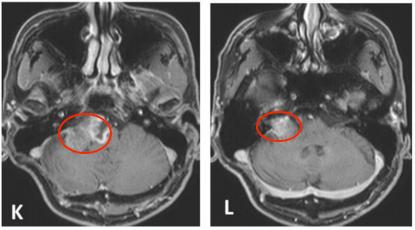

K和L.2014年4月轴位钆剂(Gd)增强T1加权MR图像,显示不均匀强化伴有脑干受压,行第三次手术切除。M和N.在第三次手术切除后2个月随访的轴位钆剂(Gd)增强T1加权MR图像。

2004年5月,采取右侧乙状窦后入路切除肿瘤。术中肿瘤质地坚实(solid),血管相对丰富,易出血,部分切除肿瘤(图1A-B),于2005年8月行伽玛刀放射外科治疗(GKS)(图2)以控制当时的残留肿留。2007年5月行第二次手术切除,因蛛网膜边缘不清,与面听神经和后组颅神经粘连严重,残留部分肿瘤囊壁(图1C-D)。病人每6个月定期随访脑部MRI(图1E-I),最初的残留肿瘤的大小是稳定的。2013年11月,常规随访MRI显示肿瘤开始生长(图1J)。2014年4月出现进行性头痛、眩晕、和恶心,MRI显示肿瘤肿块增大。2014年6月(图1K-L)进行次全肿瘤切除,术中发现显示,肿瘤有两个部分,也就是说,有一部分是软的且相对容易切除,另一部分有弹性伴有纤维组织,蛛网膜边界不清楚,与面听神经和后组颅神经严重粘连。本病例的第二次及第三次手术均由同一位神经外科医生完成。